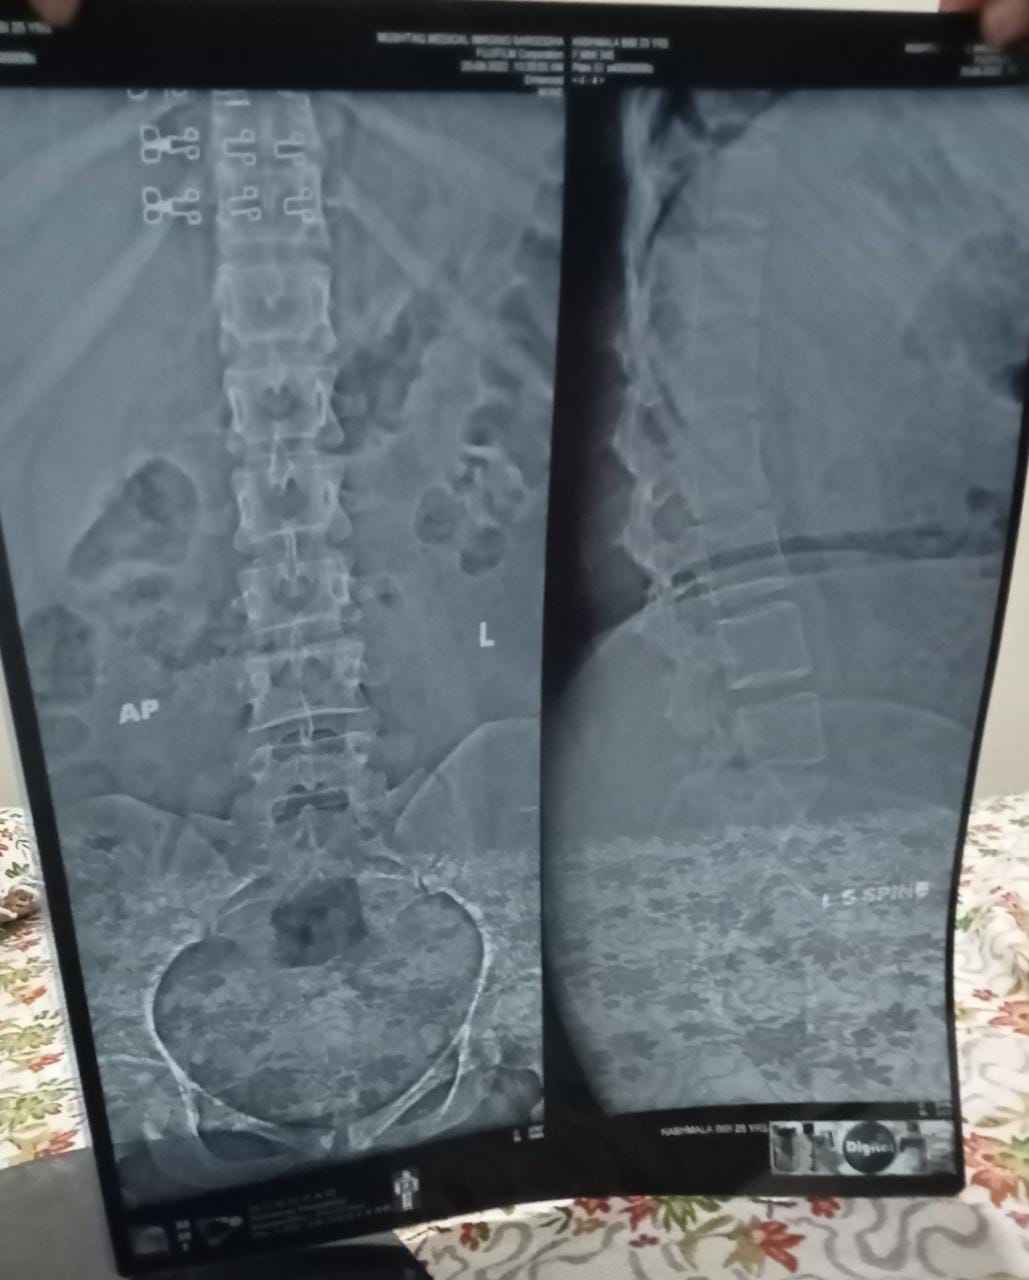

Asking for Self, Female, 26 years old, Sargodha

Neck shoulder back pain hai tangon or paon mein bhi Thora wazn prny Sy tangon or paon sun ho jaty hein